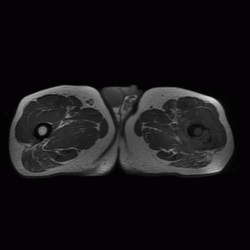

Патология костной структуры. Динамика. Ваше мнение?

Из анамнеза: 6 мес назад была травма. Не обращался,не лечился. Боли сохранялсиь,в последнее время усиливаются.

cпециалист по МРТ выставляет остеомиелит. направлен на открытую трепанбиопсию.Буде информация-сообщу.

Биопсия это единственно правильно, на мой взгляд, больше данных за онкологию, но здесь обширный ряд: от той же саркомы Юинга (остеосаркомы, ЗФГ) до мтс, т.е имеет место некий весьма агрессивный процесс в виде остеолитической деструкции, инфильтрации кости. М.б. и поднадкостничная гематома, осложнившаяся остеомиелитом, но за полгода воспалительный процесс должен был как-то себя проявить...

Мне кажется, уже по первому снимку можно было онкологию выставлять.